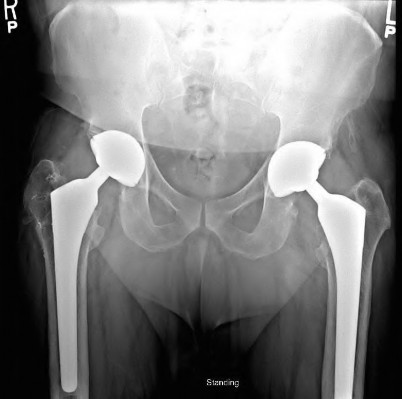

A 72-year-old female presents with progressive left thigh and knee pain for the last year. 5 years ago she sustained a femoral neck fracture treated with the implant seen in Figures A-C (current radiographs). The thigh pain is worse with weight-bearing. C-reactive

protein and erythrocyte sedimentation levels are within defined limits. Which of the following is the most likely cause of her pain?